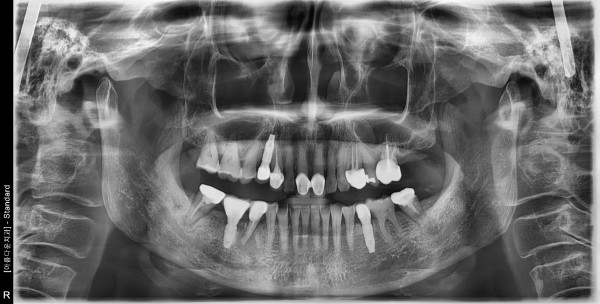

60대 여성 임플란트 식립

e42e986bdfcf919f5813591835ea9a60_1759110